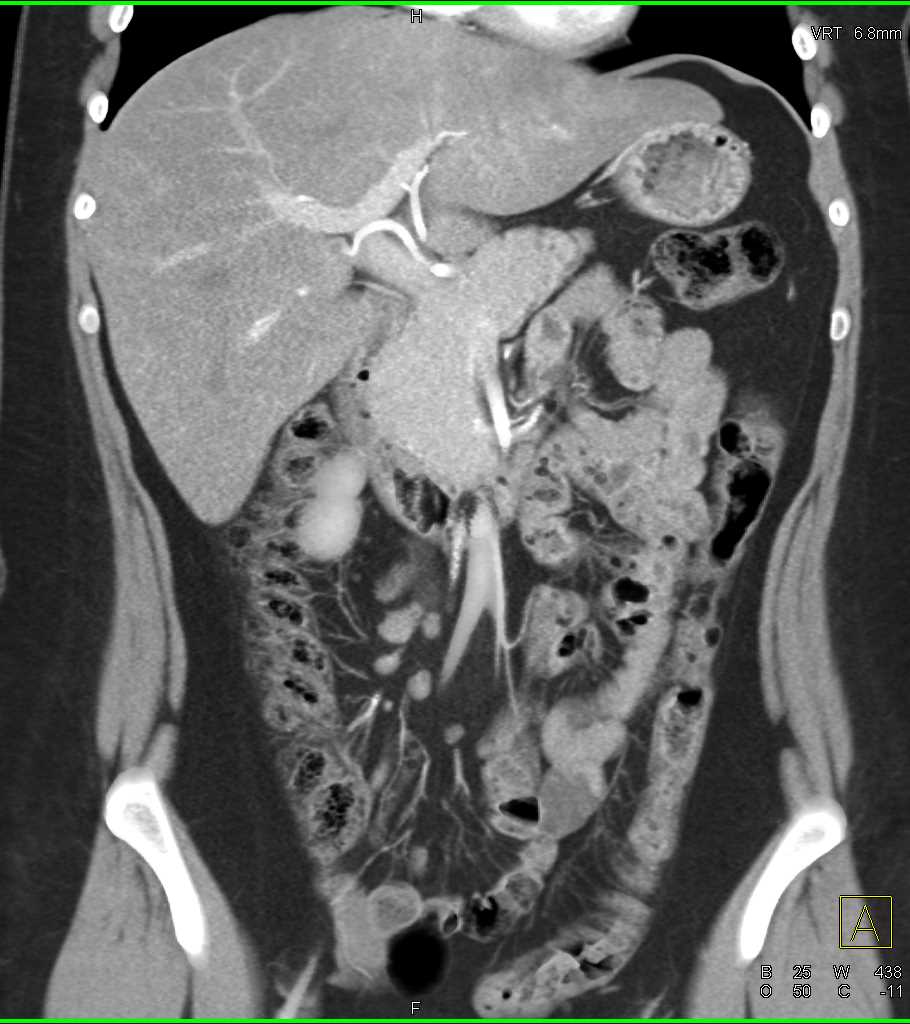

Vasculitis with Mesenteric Vascular Involvement